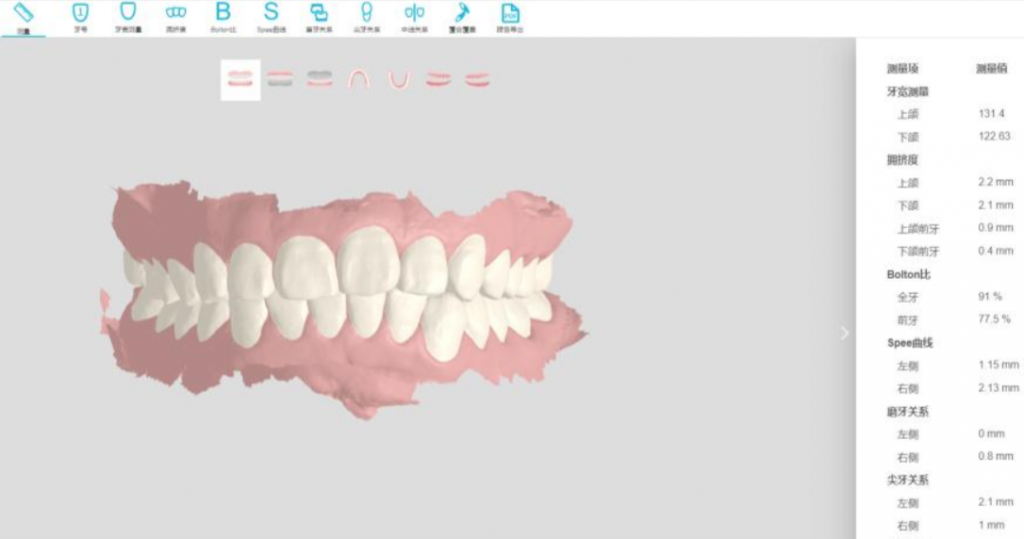

STEP 2: AI-Powered Decision Engine

Treatment System

1、98.7% caries detection accuracy (9.2% above human experts)

2、Personalized treatment plan designs,effective visual

communication via and predictable treatment outcomes.

3、Generates 3 treatment plans with cost/duration/success comparisons

Case Study: Implant acceptance rate ↑91% at Jakarta Clinic